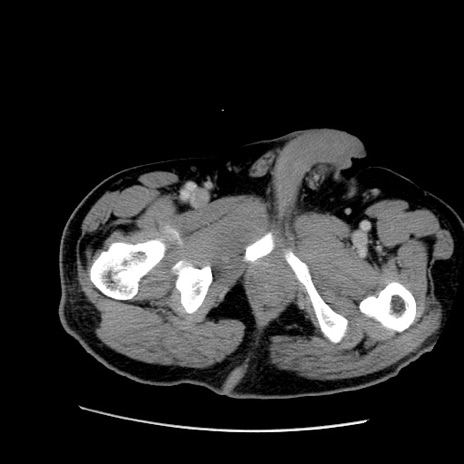

症例22(横断像)

【症例】50歳代男性

【主訴】腹痛

【現病歴】AVMからの被殻出血のため回復期リハ病棟入院中。 本日午後3時頃急に下腹部痛が出現した。

【既往歴】AVM、被殻出血、虫垂炎、高血圧

【身体所見】意識晴明、左半身不全麻痺、会話の理解は良好、36.5°C、腹部:膨隆、全体に板状硬、下腹部正中に圧痛点あり、反跳痛-、筋性防御不明、右下腹部にope scar

【データ】WBC 9400、CRP 0.06